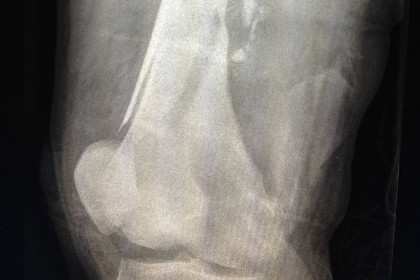

В своей работе инженеры для имитации кровоизлияния в поврежденной части человеческого тела использовали гидродинамику сглаженных частиц. Для этого с учетом необходимых анатомических особенностей (расположения костей, мышц, сосудов и кожи) исследователи провели трехмерную реконструкцию человеческой ноги.

На примере деформированной баллистическим снарядом человеческой ноги специалисты изучили процессы внутреннего и внешнего кровоизлияний. Инженеры рассмотрели два сценария ранения: в первом случае нога человека расположена вертикально, тогда как во втором случае она расположена горизонтально.